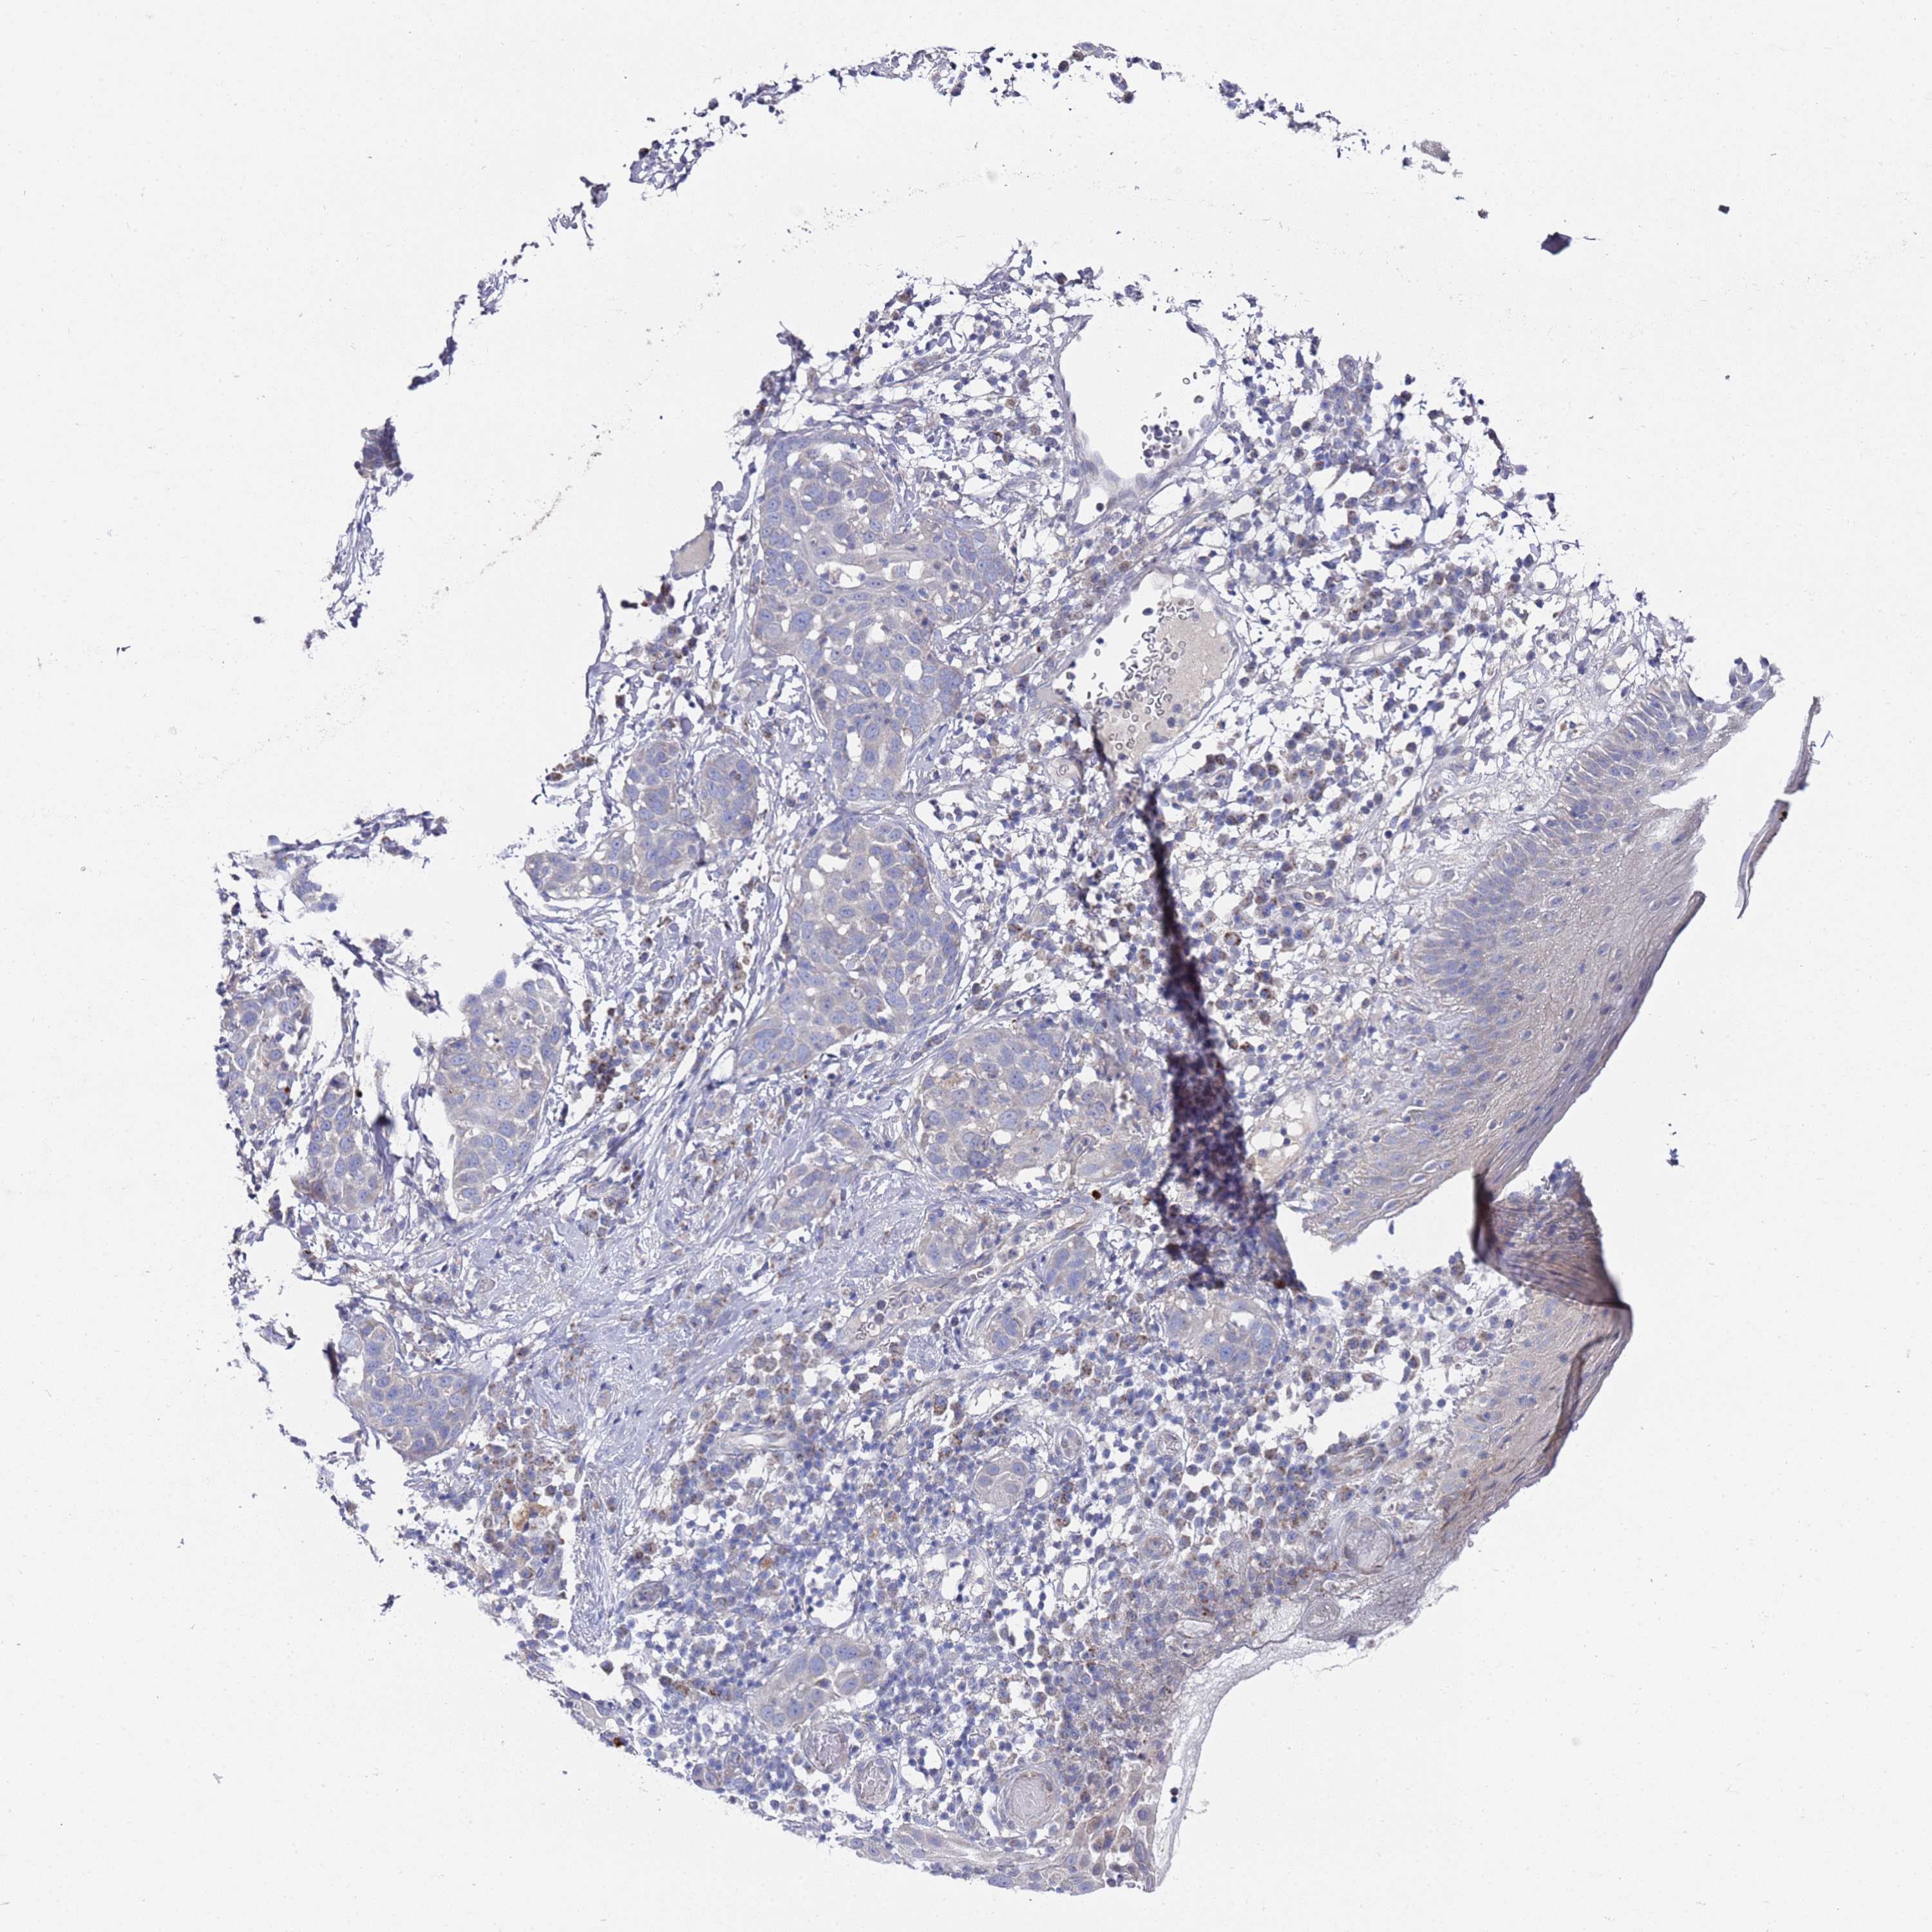

SKIN CANCER - Protein expressioni

A mouse-over function shows sample information and annotation data. Click on an image to view it in a full screen mode. Samples can be filtered based on level of antibody staining by selecting one or several of the following categories: high, medium, low and not detected. The assay and annotation is described here.

Each image is clickable and will lead to virtual microscopy that enables deeper exploration of all samples and also displays staining intensity scores, fraction scores and subcellular localization as well as patient and tissue information for each sample.

Antibody HPA045649

Basal cell carcinoma